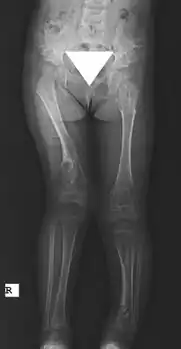

Maffucci syndrome -

X-ray hips and legs: multiple enchondroma -

X-ray legs: Ollier disease -